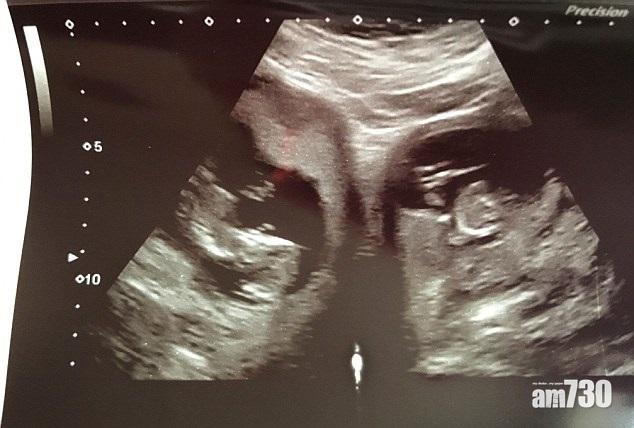

英國一名孕婦前往醫院檢查,不但驚悉自己有兩個子宮腔,更發現兩子宮同時受孕,醫生指這種情況的機會率約為5億分一。31歲、來自康沃爾郡坎伯恩(Camborne)的阿士活德(Jennifer Ashwood),與丈夫育有一名8歲女兒,今年2月再懷孕20周時到醫院接受產前檢查,才驗出有「雙子宮」,全球有此特徵的人不足100人。更罕見的是,多數有雙子宮的女性只會有一邊子宮懷孕,但她卻是兩邊子宮同時懷孕,並於懷孕34周後剖腹誕下一子一女。她說:「你或以為很了解自己的身體,但原來並不是。」她又表示很享受一家五口的生活,「現在家裡很忙,我們沒有太多睡眠時間,但就算只有一個孩子,我們也睡得很少。現在我們有了雙倍的擁抱和愛。」